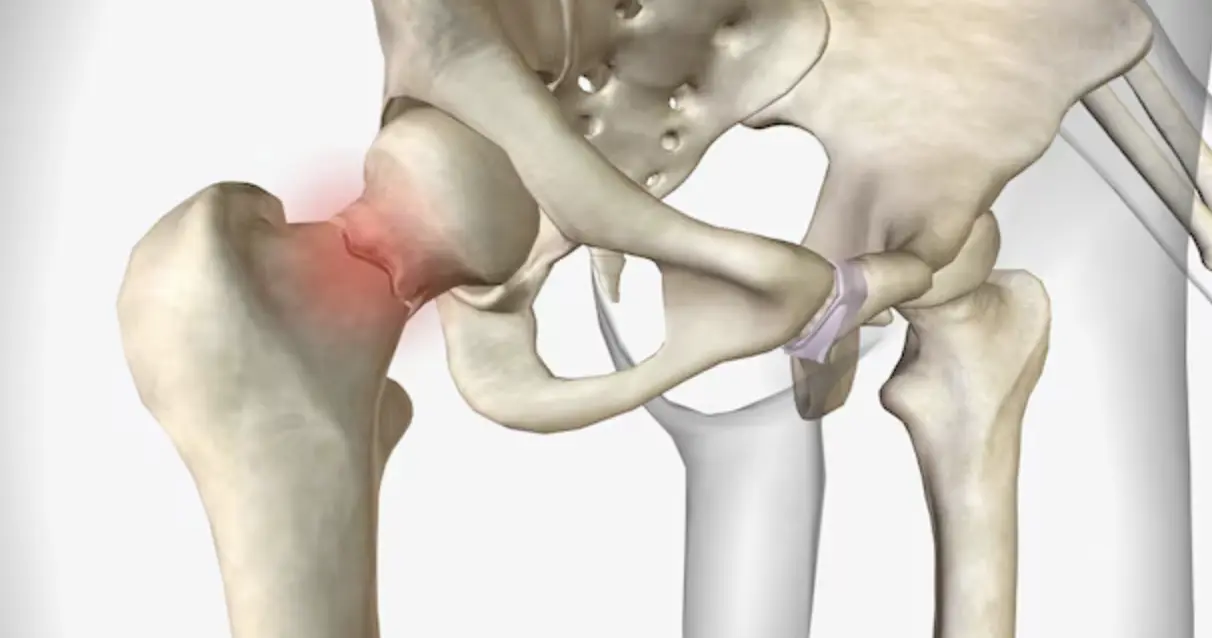

1. يوتا سۆڭەك بوينى سۇنۇش: ياشانغانلارنىڭ ئاخىرقى سىنىقى

يوتا سۆڭەك بوينى سۇنۇش كۆپىنچە «ياشانغانلارنىڭ ئاخىرقى قېتىملىق سۇنۇقى» دەپ ئاتىلىدۇ. بۇنىڭ ئاساسلىق سەۋەبى، بۇ قىسىمنىڭ قان بىلەن تەمىنلىنىش سىستېمىسى ئىنتايىن ئاجىز ۋە ئۆزگىچە بولۇپ، سۇنۇق يۈز بەرگەندىن كېيىن قان تومۇرلار ئاسانلا زىيانغا ئۇچرايدۇ. قان يېتەرلىك بولمىغاندا، سۆڭەك ھۈجەيرىلىرى قايتا ھاسىل بولالمايدۇ.

- ياشانغانلاردا سۆڭەك شالاڭلىشىش سەۋەبىدىن ئادەتتىكى يىقىلىپ چۈشۈشتىمۇ يوتا سۆڭەك بوينى ئاسانلا سۇنىدۇ.

- ياشلاردا بولسا ئادەتتە يۇقىرى ئېنېرگىيەلىك زەخىملىنىش (مەسىلەن، ئاپتوموبىل ۋەقەسى) سەۋەبىدىن كۆرۈلىدۇ.

- بۇ تۈردىكى سۇنۇقنىڭ ئەڭ چوڭ خەۋپى شۇكى، ئۇ ئۇزۇن مەزگىل ساقايماسلىق ياكى سۆڭەك بېشىنىڭ چىرىشىنى كەلتۈرۈپ چىقىرىدۇ.

بۇ خىل ئەھۋالدا، نۇرغۇن بىمارلار ئوپېراتسىيە قىلىپ سۆڭەكنى مىخلاشقا ياكى سۈنئىي بوغۇم ئالماشتۇرۇشقا مەجبۇر بولىدۇ. ئەگەر ۋاقتىدا ۋە توغرا بىر تەرەپ قىلىنمىسا، بىمارنىڭ ئۇزۇن مۇددەت ياتاقتا يېتىپ قېلىشىنى كەلتۈرۈپ چىقىرىپ، ئۆپكە ياللۇغى ياكى كارىۋات جاراھىتى قاتارلىق خەتەرلىك ئەگەشمە كېسەللىكلەرگە يول ئاچىدۇ.